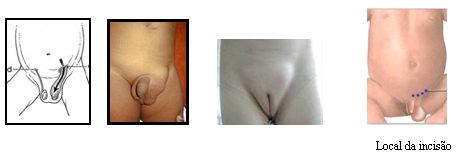

Para se tornar um Cirurgião Pediátrico, o médico precisa fazer dois anos de residência em Cirurgia Geral e mais três anos de residência em Cirurgia Pediátrica, onde verá as diferenças existentes no tratamento dispendidos a um adulto e a uma criança, ganhando habilidade no manuseio desses pacientes tão especiais. Normalmente as cirurgias são mais delicadas, realizadas sob anestesia geral e não necessitam de dormir no hospital (porém muitas delas podem ser realizadas em regime de Hospital Dia com internação que varia de 6 a 12 h). Casos cirúrgicos comuns em crianças são as hérnias inguinal e umbilical, cistos da região do pescoço como os branquiais e o tireoglosso, testículos que não estão situados na bolsa testicular, hipospádia e outras malformações do aparelho urinário, fimose, anquiloglossia (“língua presa”), tumores e doenças gastrointestinais.